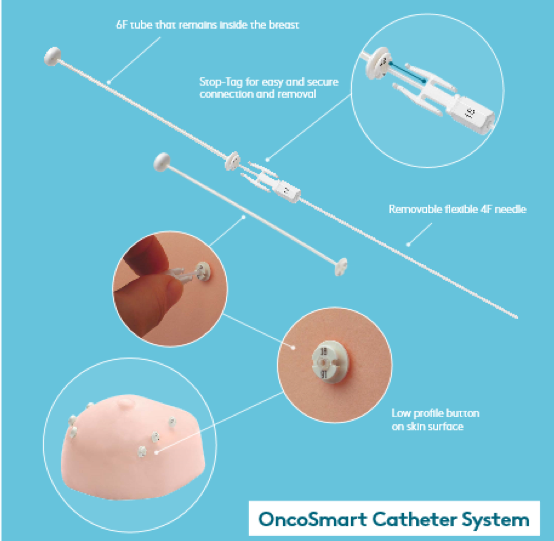

针对乳腺癌近距离治疗,医科达提供了多款施源器。OncoSmart导管系统与乳腺CT/MR模板相结合,可为放疗医师实施APBI(部分乳腺加速照射)治疗提供优秀的解决方案,给患者及其治疗带来极佳的灵活性。

针对乳腺癌近距离治疗,医科达提供了多款施源器。OncoSmart导管系统与乳腺CT/MR模板相结合,可为放疗医师实施APBI(部分乳腺加速照射)治疗提供优秀的解决方案,给患者及其治疗带来极佳的灵活性。

OncoSmart导管系统与乳腺CT/MR模板相结合,可为放疗医师实施APBI(部分乳腺加速照射)治疗提供优秀的解决方案,给患者及其治疗带来极佳的灵活性。

该系统是专为部分乳腺加速照射(APBI)设计的完整套件。医科达为乳腺癌治疗提供了一系列近距离治疗方案。OncoSmart导管系统与乳腺CT/MR模板相结合,为乳腺癌治疗提供了优秀的解决方案。